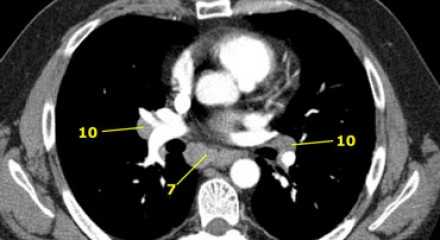

На изображении слева 3А узел в преваскулярном пространстве. Обратите внимание так же на ниже расположенные паратрахеальные узлы справа относящиеся к 4R группе.

4R. Правые нижние паратрахеальные лимфатические узлы

- Верхняя граница: пересечение нижнего края левой плечеголовной вены с трахеей.

- Нижняя граница: нижний края непарной вены. 4R узлы распространяются до левого края трахеи.

На изображении слева мы видим 4R паратрахеальные узлы. Кроме того здесь представлен узел кнаружи от дуги аорты, то есть 6 группы.

На левом изображении над уровнем легочного ствола представлены нижние паратрахеальные узлы слева и справа, так же здесь представлены узлы 3 и 5 групп.

Изображение слева выше уровня карины. Слева от трахеи 4L узлы. Обратите внимание что они расположены между легочным стволом и аортой, но не в аортопульмональном окне, потому что они лежат медиальнее артериальной связки. Лимфатические узлы латеральнее легочного ствола относятся к 5 группе.

![11]() 7. Подкаринальные лимфатические узлыЭти лимфатические узлы расположены ниже уровня бифуркации трахеи (карины), но не относятся к нижнедолевым бронху и артерии. Справа они располагаются каудальнее нижней стенки промежуточного бронха. Слева они располагаются каудальнее верхней стенки нижнедолевого бронха. Слева лимфатический узел 7 группы справа от пищевода. ![12]() 8. Параэзофагеальные лимфатические узлыЭти лимфатические узлы ниже подкаринальных лимфатических узлов и распространяются каудальнее до диафрагмы. На изображении слева ниже уровня карины справа от пищевода обозначен лимфатический узел 8 группы. На ПЭТ изображении слева показано накопление 18Р-дезоксиглюкозы в узле 8 группы. На соответствующем КТ изображении видно что данный лимфатический узел (голубая стрелка) не увеличен. Вероятность того что в имеется метастатическое поражение данного узла чрезвычайно высока, поскольку специфичность ПЭТ выше чем измерение размеров лимфатических узлов. ![14]() 9. лимфатические узлы легочной связкиДанные лимфатические узлы лежат в пределах легочной связки, в том числе и по ходу нижней легочной вены. Легочная связка представлена дупликатурой медиастинальной плевры охватывающей корень легкого. ![15]() 10. лимфатические узлы корня легкогоЛимфатические узлы корня расположены проксимальнее долевых узлов, но дистальнее медиастинальной дупликатуры и узлов промежуточного бронха справа. Все лимфатические узлы 10-14 групп являются N1 узлами, так как они находятся вне средостения. 1. лимфатические узлы вырезки грудины видны только на этом уровне и выше него 2. верхние паратрахеальные лимфатические узлы: ниже ключиц , справа над пересечением нижнего края левого плечеголовного ствола и трахеи, а слева над дугой аорты